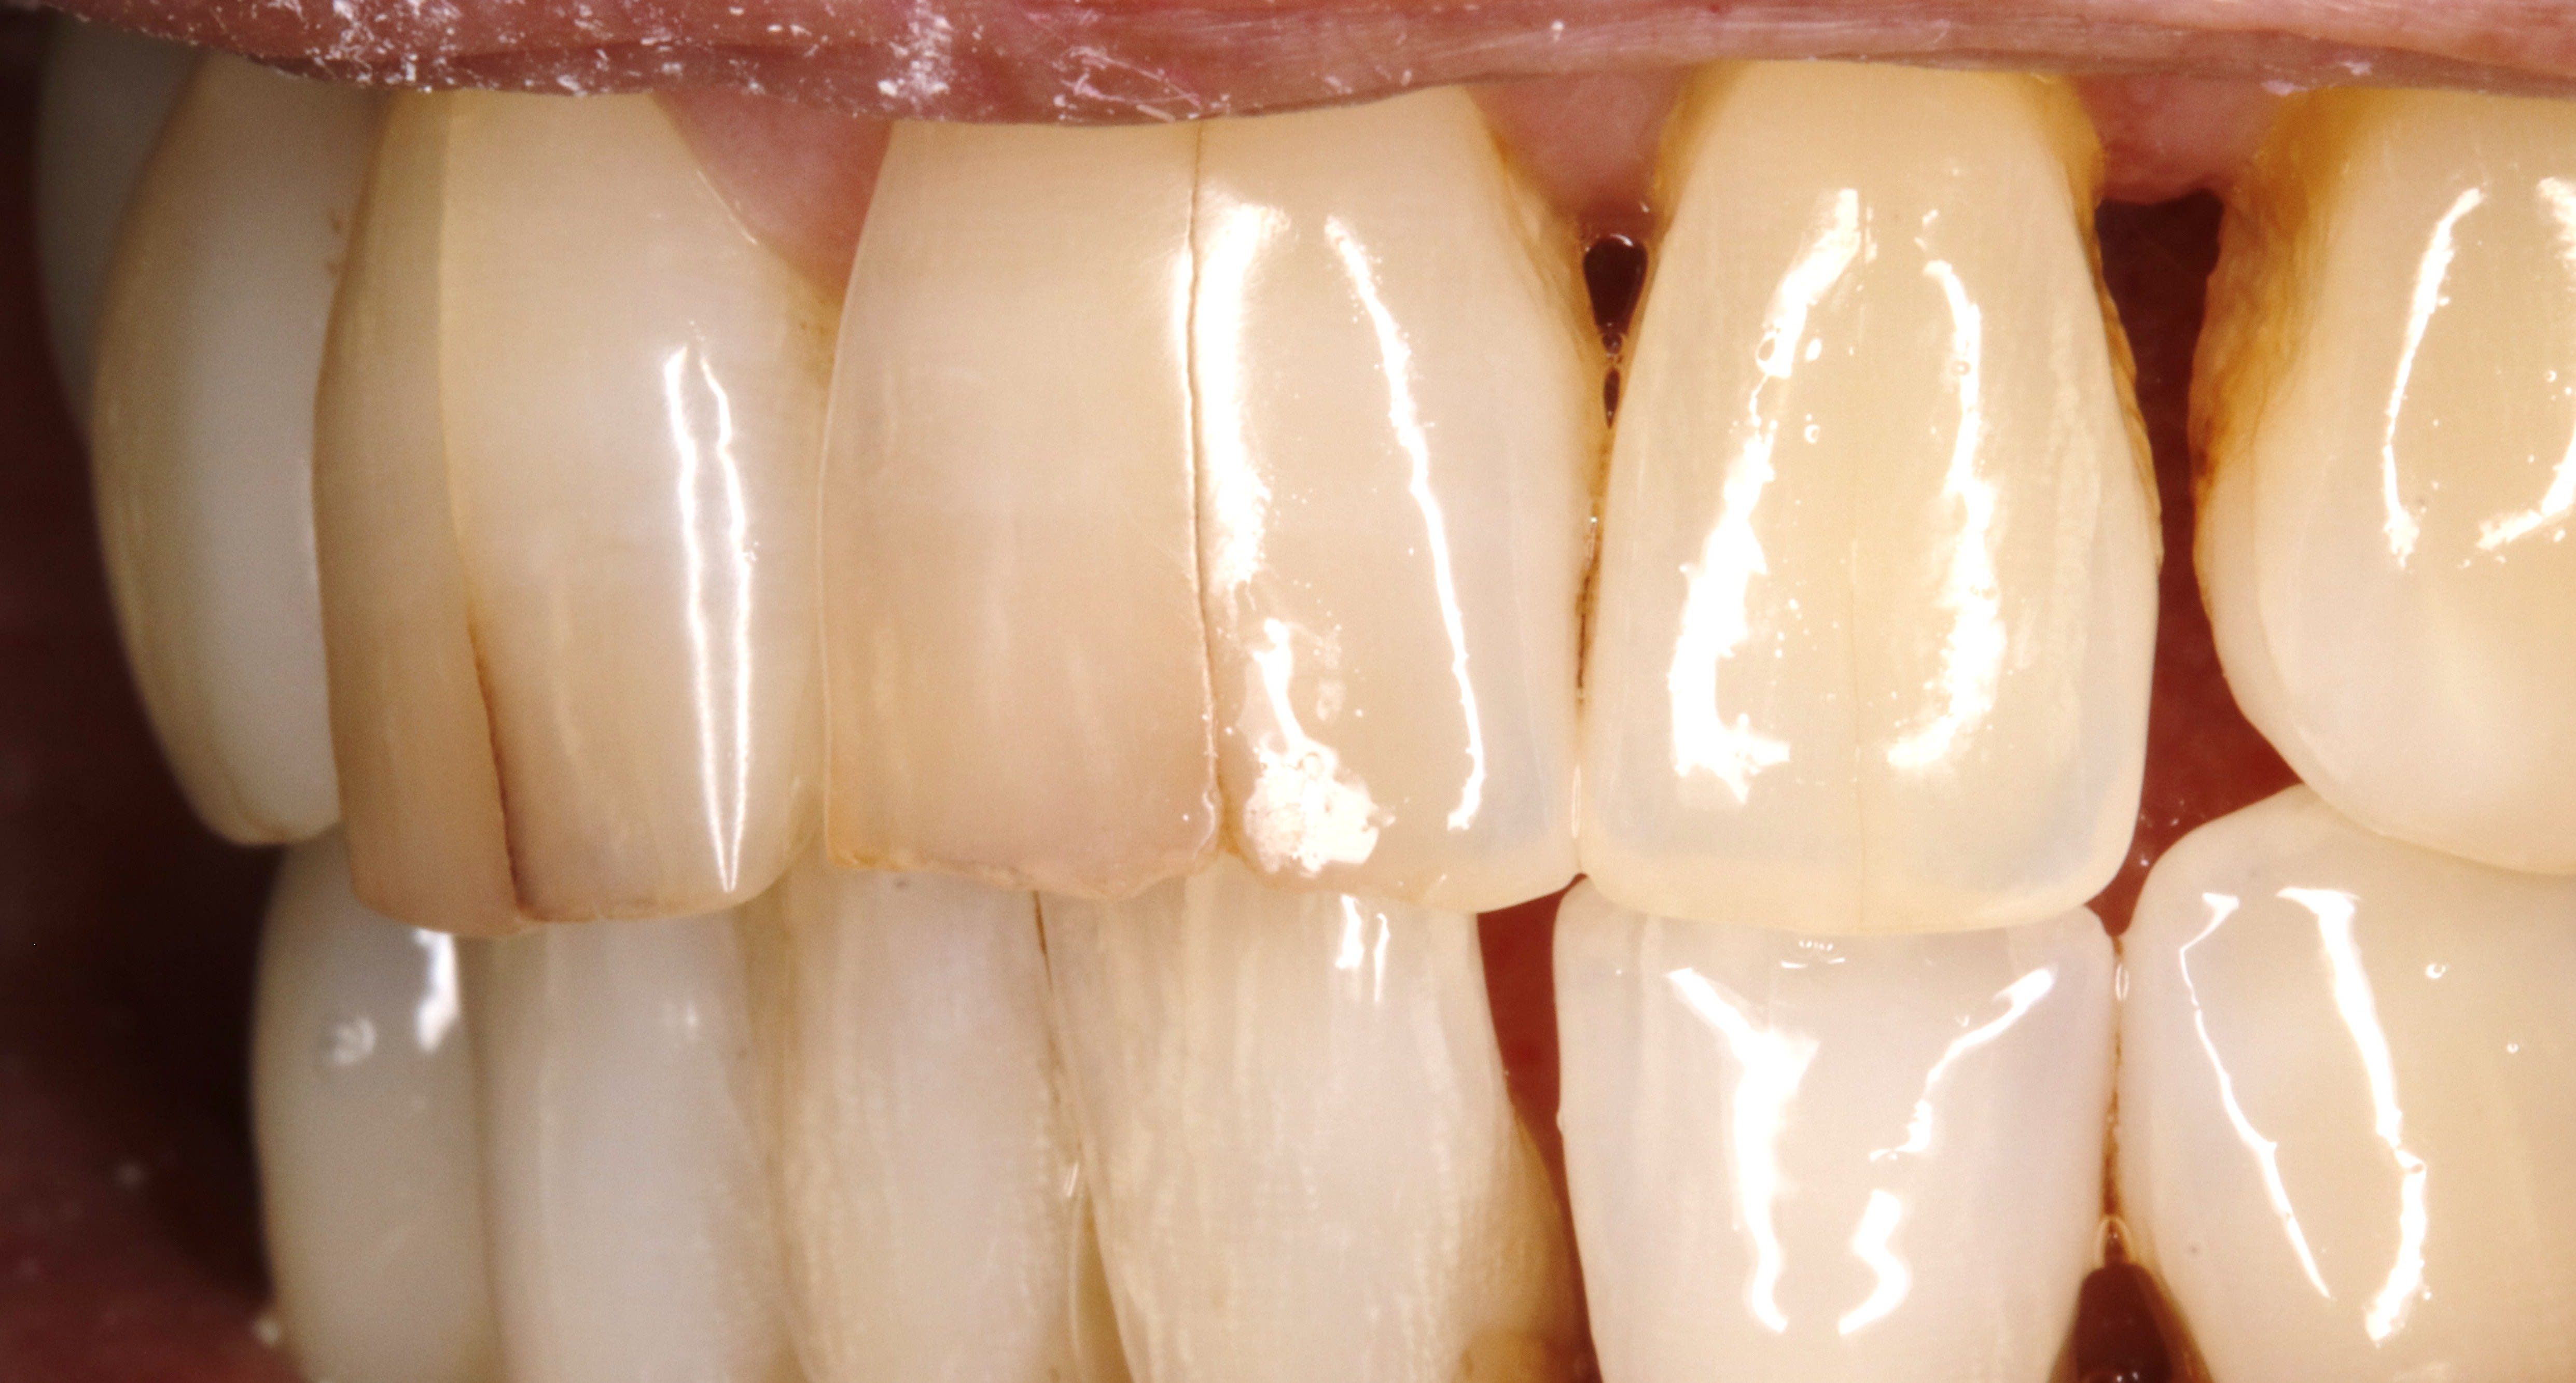

J'ai eu un cas comme ça pour une mamie de 86 ans qui voulait se faire pécho par le père Noël.

Pour les prov, j'ai fait comme Dr_EG a dit.

Les tofs sont pas terribles et le rendu final est mieux mais bon suis pas photographe non plus, à peine dentiste.